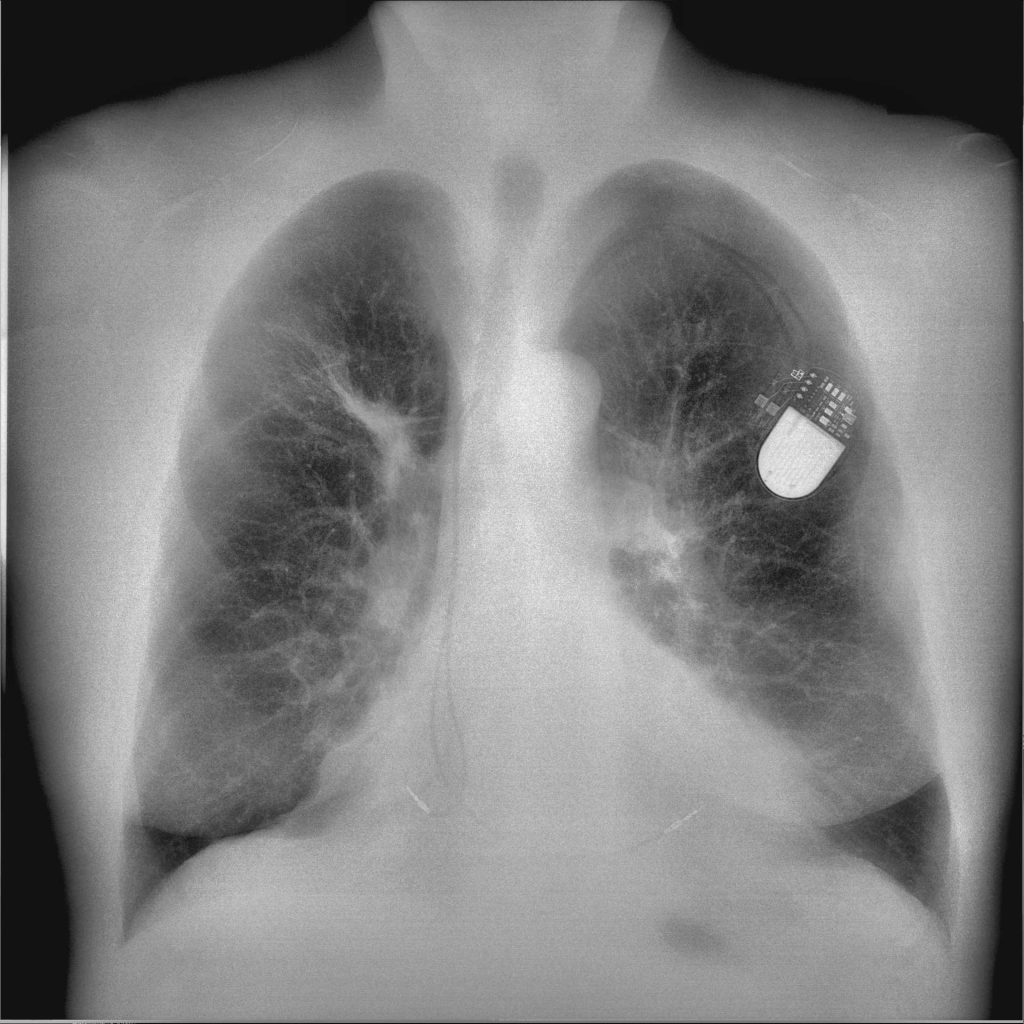

What is DQE in Radiology

On the left is the traditional DR image, in the middle is the soft tissue image, and on the right is the bone image.